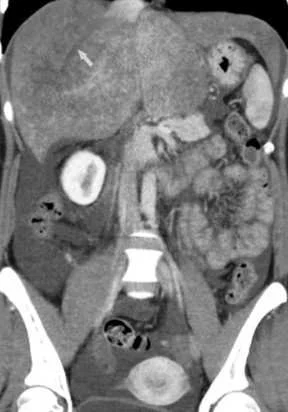

【113-1 醫學(五) 第74題】14 歲女性病人主訴右肩痠痛約半年,肩部 X 光片如圖,最可能的診斷為何?